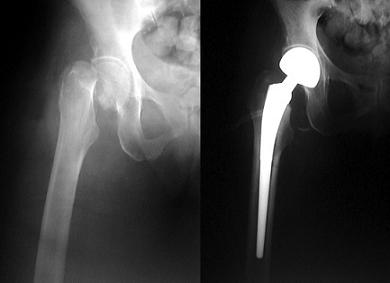

So what are we to do? The fact that there are 1.5 MILLION osteoporosis related fractures in the US every year makes this a massively important topic. Here is what a typical femoral neck fracture looks like before and after total hip replacement.